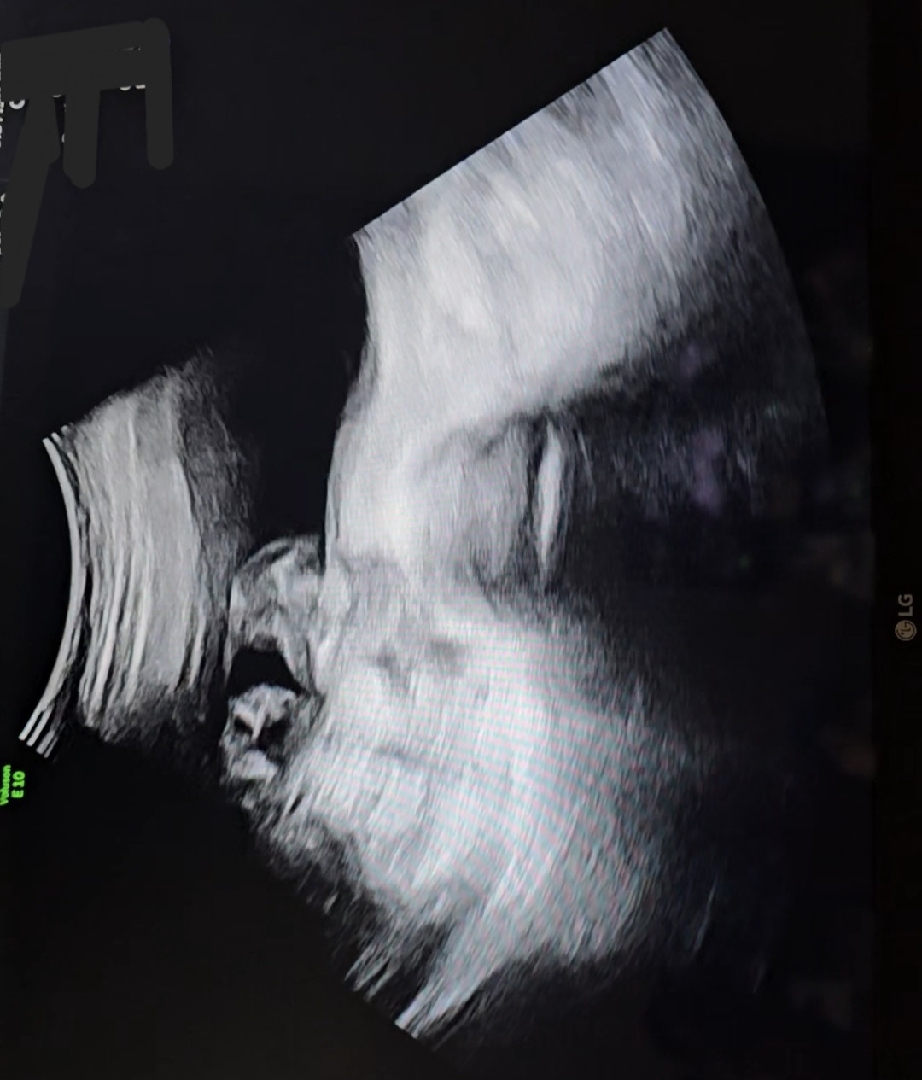

15주2일차 2차 기형아검사 초음파받았는데 성별이 뭘까요..ㅜㅜ 도와주세요

제가 봤을땐 딸인느낌인데.. 병원에서 성별을 아직 안알려줘서요.. 너무 궁금해서 고수님들께 여쭤봅니다!! ㅜ.ㅜ

위에 캡쳐 전 엉덩이 쪽이에요!